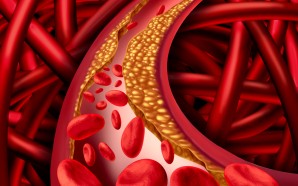

For proper functioning, your body requires lipids, also known as cholesterol which is produced by the liver or contained in some foods. Cholesterol on its own doesn’t cause any health symptoms, though in excess it could cause complications like heart disease. To move around the body, cholesterol combines with proteins,...

A balanced, healthy diet and regular exercise are extremely important when trying to manage cholesterol levels. If diet and exercise do not improve your overall cholesterol levels quick enough, intervention may be needed. Your doctor may prescribe you a statin, like . is a statin medication that can improve...

Aside from one other drug, there haven’t been any good non-statin medications used to treat high LDL levels. Often, statin drugs like Crestor, Lipitor, and Zocor have been prescribed to lower the ‘bad’ cholesterol that clogs arteries, which, in turn, puts individuals at risk of cardiovascular disease. These treatment options have...